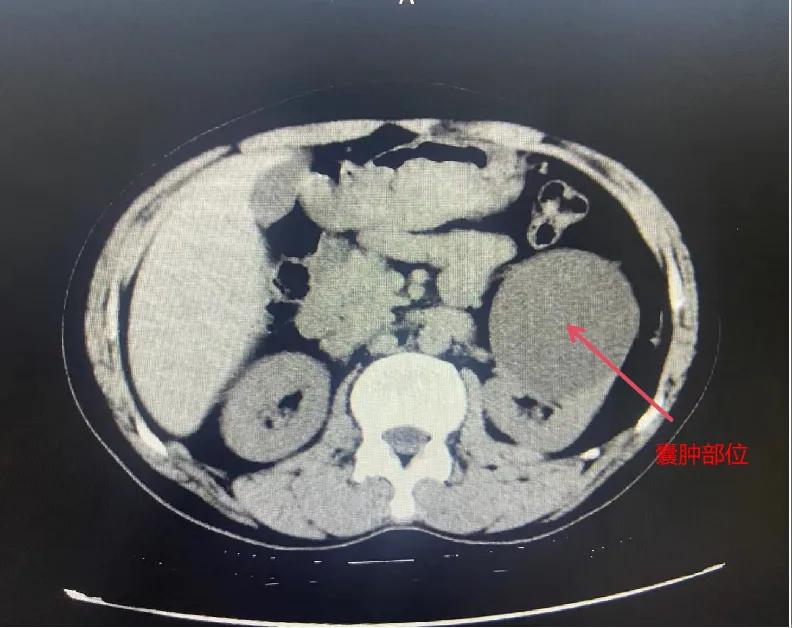

漯河市骨科醫(yī)院泌尿外科開展后腹腔鏡下腎囊腫去頂減壓術(shù)

近日,漯河市骨科醫(yī)院(漯河醫(yī)專二附院、漯河市立醫(yī)院)連續(xù)收治2例腎囊腫患者。泌尿外科主任閆衛(wèi)甫和副主任醫(yī)師王金柱等醫(yī)師團隊經(jīng)討論研究后,決定為患者采取后腹腔鏡下腎囊腫去頂減壓術(shù),經(jīng)過手術(shù)室、麻醉科等科室大力配合成功完成手術(shù)。

腎囊腫是一種常見的腎臟良性疾病,其發(fā)病率逐年增加。近年來隨著腹腔鏡技術(shù)的迅速發(fā)展,后腹腔鏡下腎囊腫去頂減壓術(shù)成為治療腎囊腫的主要方法。該手術(shù)具有創(chuàng)傷小,手術(shù)時間短,術(shù)中出血少,術(shù)后康復(fù)快,出院時間短等優(yōu)點,并且術(shù)后復(fù)發(fā)率低,被認為是治療腎囊腫的理想術(shù)式。(盧 闖 聶方方 劉 旭 袁錦鈺)